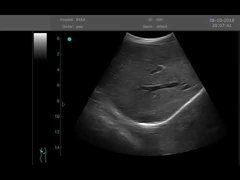

Kwaliteit Draagbare ultrasone Scanner, handbediende Ultrasone klankscanner Fabrikant uit China

Alle video's